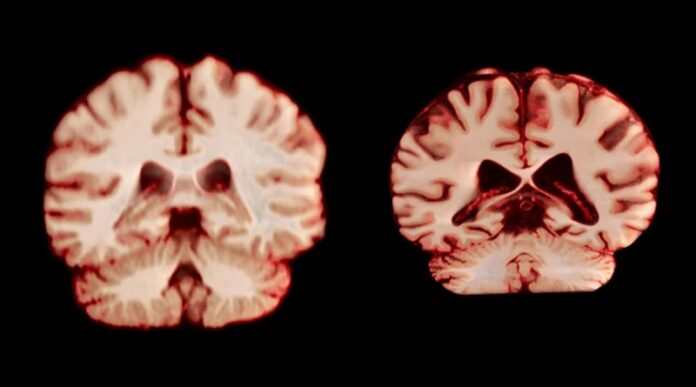

Un nuevo estudio publicado en la revista Nature sobre las implicaciones que las diferencias de género en el envejecimiento cerebral tienen en el alzhéimer revela que los hombres experimentan una mayor reducción de volumen en más regiones del cerebro que las mujeres.

Tras examinar las diferencias de tamaño cerebral basadas en el sexo, el equipo descubrió que los hombres mostraban un deterioro en un mayor número de regiones cerebrales, incluidas muchas partes de la corteza, a edades más avanzadas. Estos hallazgos evidencian que la mayor prevalencia de diagnósticos de alzhéimer en las mujeres probablemente se deba a factores que van más allá de las tasas diferenciales de atrofia cerebral relacionada con la edad.